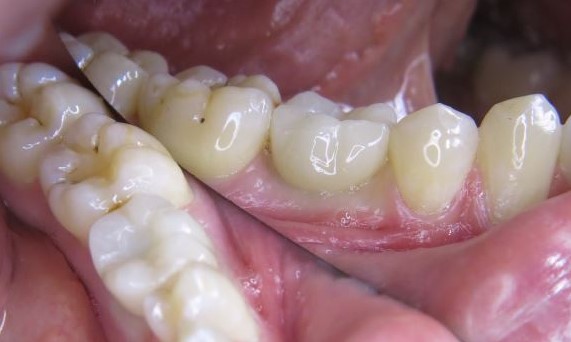

Harmonische und vereinfachte Arbeitsabläufe vom präzisen Intraoralscan bzw. der konventionellen Abdrucknahme bis zur finalen Versorgung.

Langfristiger Knochenerhalt und exzellente Ästhetik dokumentiert und klinisch erprobt.